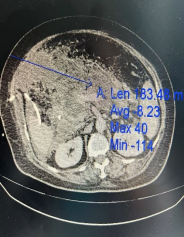

2025年3月14日我科急症收治一名64岁女性患者,BMI:32.5诊断:急性重症胰腺炎(胆源性)全身炎症反应综合征(SIRS),入院腹痛剧烈,伴腹胀发热,既往有高血压病史。辅助检查:实验室检查:血淀粉酶871 U/L,甘油三酯5.6 mmol/L,CRP 180 mg/L,乳酸3.8 mmol/L,肌酐:555.05umol/L。急性重症胰腺炎(SAP)是一种起病急、进展快、并发症多的高危疾病,死亡率可达20%-30%(根据2021年国际胰腺病协会数据)。若不及时治疗,可能引发多器官衰竭。

治疗第四周,患者再次高热,CT证实胰腺坏死灶感染并发脓毒血症。本病例遵循“Step-up approach”模式,优先微创干预,避免早期开放手术的高风险。行胰腺穿刺引流术。每日引流约600ml。治疗后患者病情逐步平稳,成功助力患者度过第二个死亡高峰期。